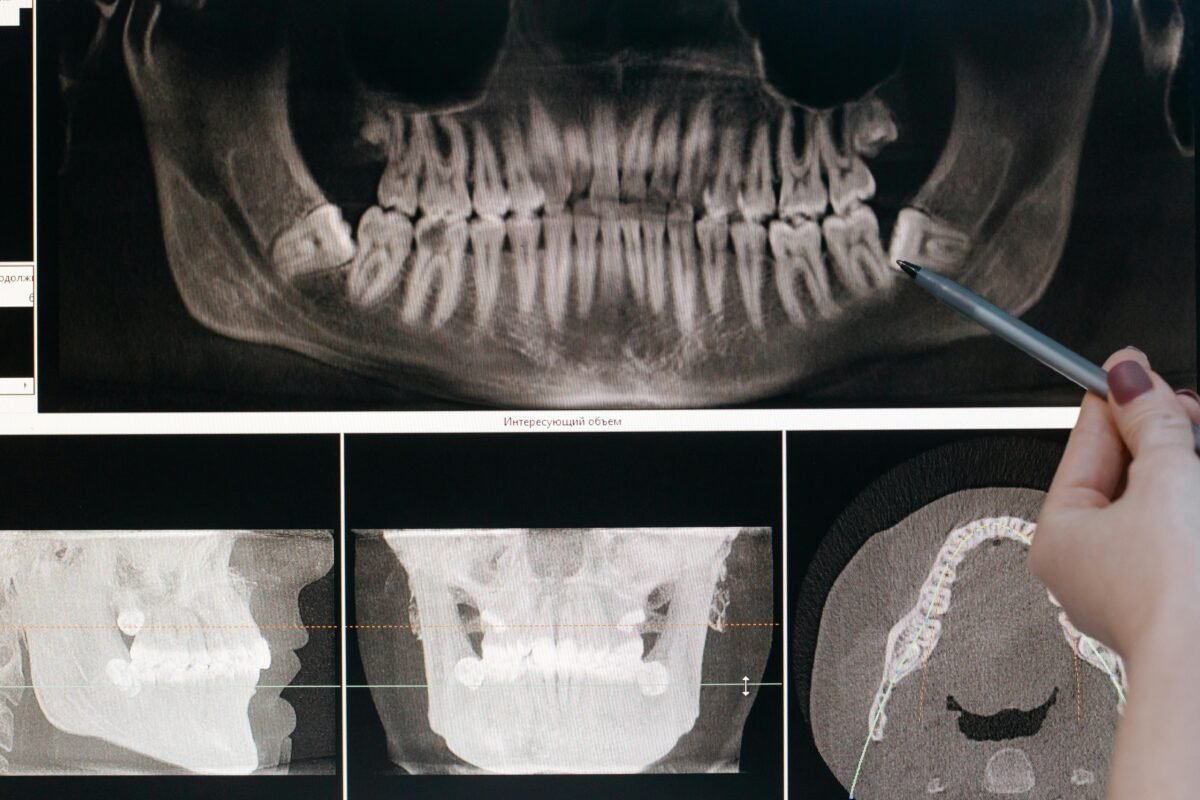

Diagnóstico Dental